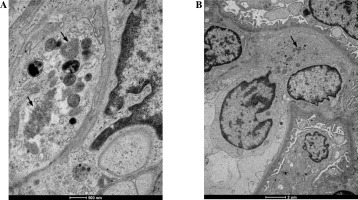

The evaluation of the biopsy samples in a light microscope revealed class III LN in five cases (50%), class II in three cases (30%), and class IV and class V in two individual cases (Table 1). Ultrastructural analysis of the biopsy material showed the presence of TRIs in seven patients (Table 3). These structures were most often found in endothelial cells of both the vascular bundle and the peritubular capillaries. They were occasionally observed in monocytes within capillaries and mesangial fields (Fig. 1). TRIs occurred within the irregularly widened cisterns of the endoplasmic reticulum. Some of them presented signs of pronounced swelling, which led to disruption of the surrounding membranes. In some inclusions, the tubular structures came into close contact with the membranes of the endoplasmic reticulum (Fig. 2). Both the size of the inclusions and the frequency of their occurrence varied among specimens (Fig. 3). The size of the TRIs varied in the range 300-1600 nm. Numerous TRIs (several inclusions in one glomerulus) were found in the biopsy of a patient with class V LN. All patients were tested for the most common viral infections connected with presence of TRIs (HIV, HBV, HCV, EBV, CMV) and all those disorders were excluded by performing simple blood tests. Only in one patient, after three years of treatment, was the re-biopsy performed. TRIs were still present in the specimen, but they were much less abundant (Fig. 4). In three cases with the highest presence of TRIs, the disease began before puberty (at 8-10 years of age), and in all these cases hematological disorders such as leukopenia, anemia, and thrombocytopenia preceded the LN diagnosis. Inclusions in a typical location, near subendothelial deposits, were observed in only one patient (Fig. 5). Biopsies of three patients with disease onset in adolescence (around 14 years of age) revealed no TRIs in the sampled material. In these patients, arthritis and nephrotic proteinuria dominated the clinical picture.

Fig. 2

A, B) Evident tubuloreticular inclusions (TRIs) visible within the degranulated rough endoplasmic reticulum in renal biopsy samples collected from patients with juvenile systemic lupus erythematosus (jSLE). Full arrowheads indicate loss of the reticular membrane continuity. Open arrowheads indicate adherence of individual tubules to the membranes of the reticulum

Fragment of a capillary with a highly swollen endothelial appendix containing three tubuloreticular inclusions (TRIs) (arrows) in renal biopsy samples collected from patients with juvenile systemic lupus erythematosus (jSLE)